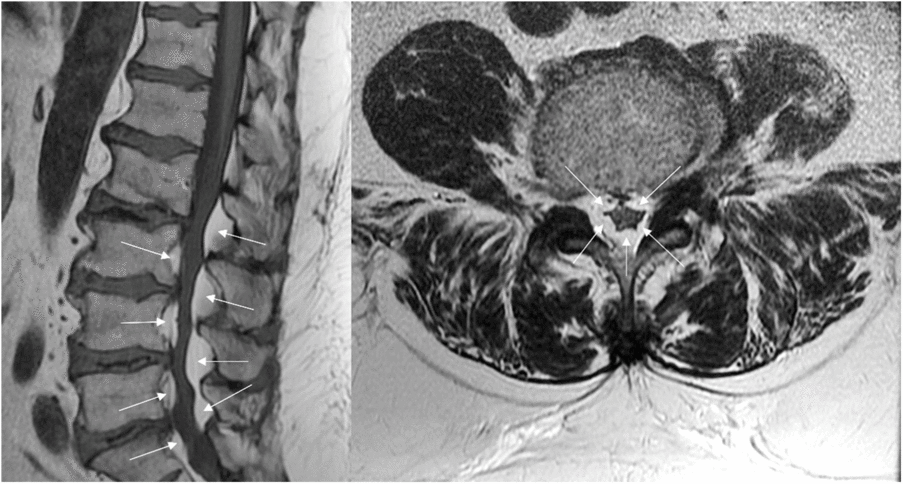

The patient was submitted to magnetic resonance imaging (MRI) of the lumbar spine that revealed a severe circumferential compression of the dural sac (from L2 to S1) caused by a relevant hypertrophy of the intracanal epidural fat (Figure 1). These findings are the characteristics of spinal epidural lipomatosis (SEL), grade 2 according to Borré, a condition already known as a rare cause of spinal stenosis.Reference Fassett and Schmidt1,Reference Borré, Borré, Aude and Palmieri2 In a previous MRI, performed 5 years before the weight gain (BMI = 33 kg/m2), for low-back pain, when claudication symptoms were not present, the epidural fat was well represented but significantly less voluminous (grade 1) (Figure 2).

Figure 1: MRI study (T1w sagittal image on the left and T2w axial image on the right) shows a circumferential compression of the dural sac due to relevant hypertrophy of spinal epidural fat from L2 to S1 (arrows).